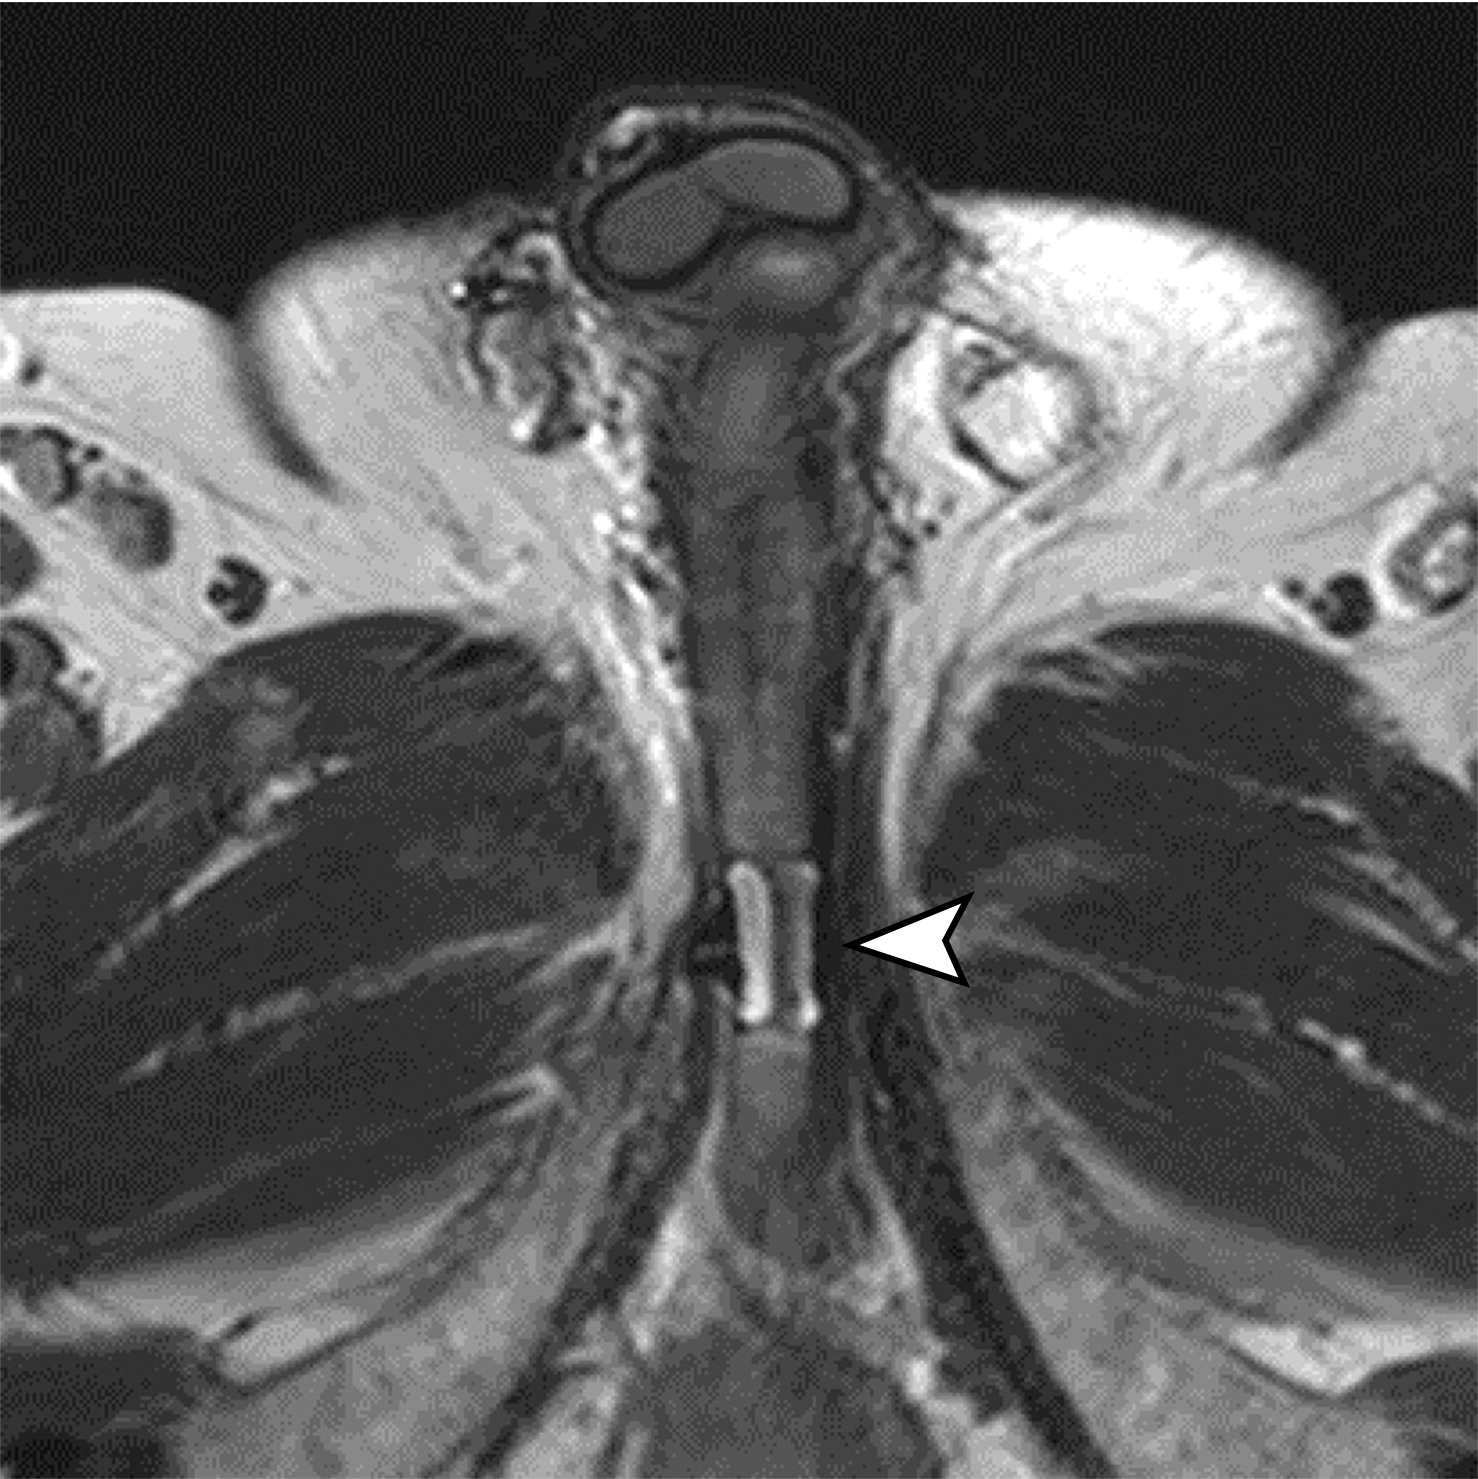

尿道吊带。

白色长箭头示尿道吊带的正常位置,正常的尿道吊带是薄的T2WI低信号影,向外延伸至闭孔。